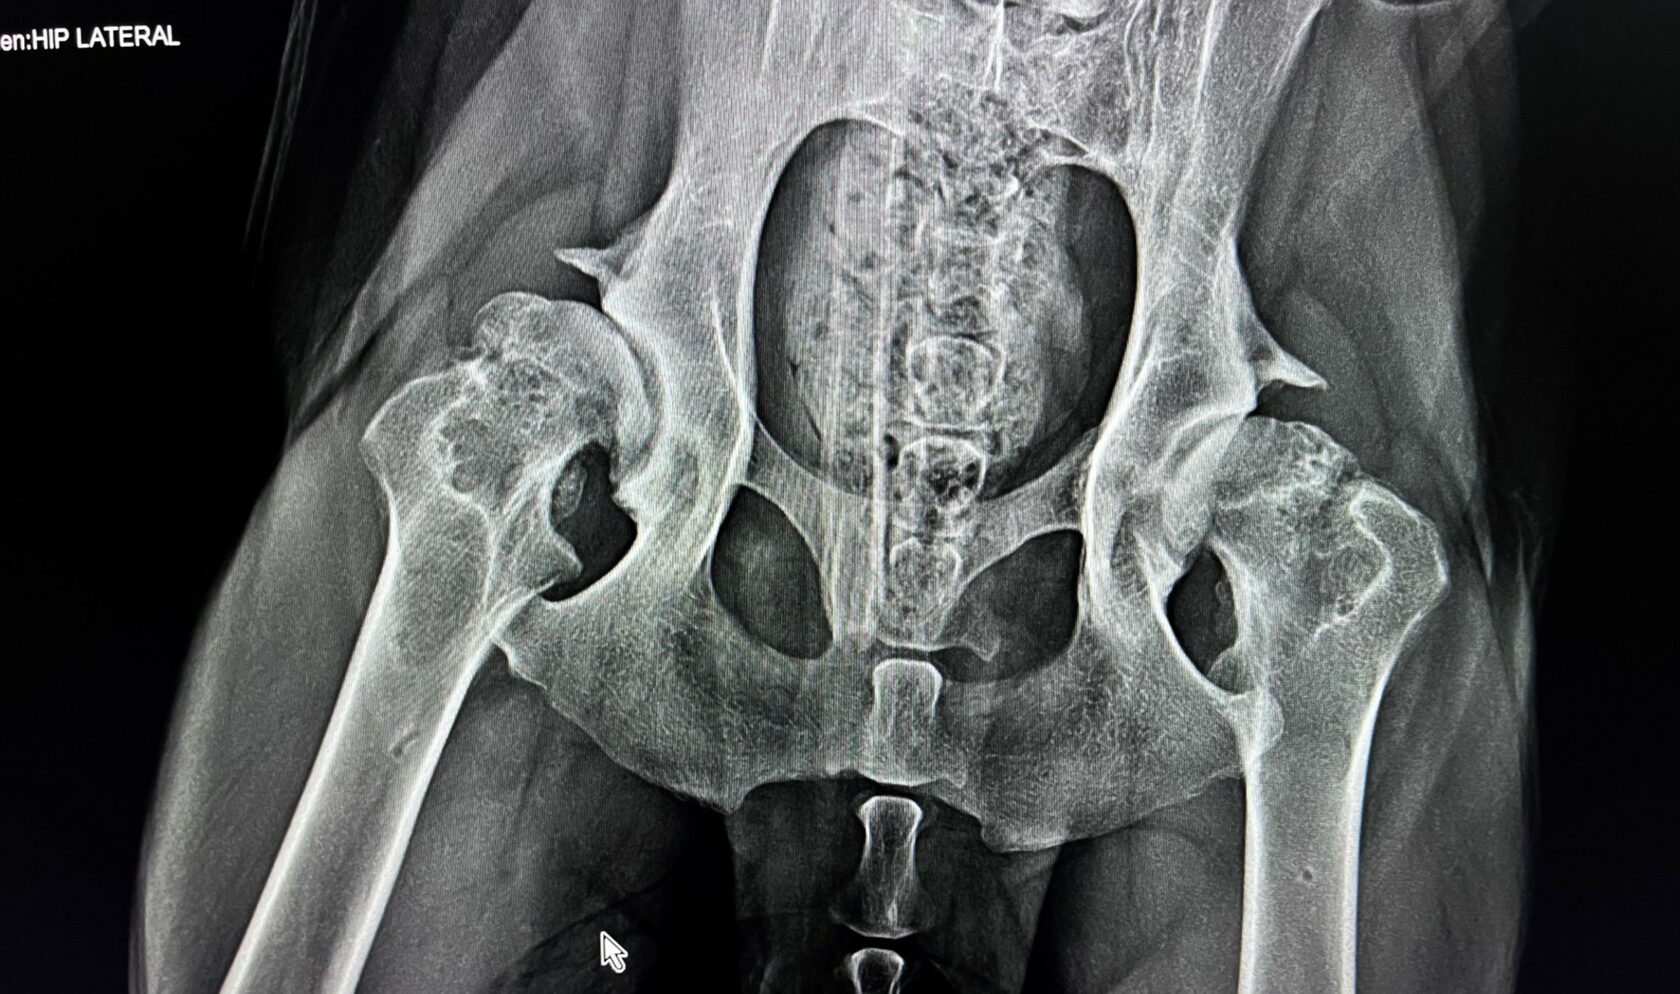

Клинический случай

Доберман, 3 года

Разрушение тазобедренных суставов вследствие остеоартрита.

Проведено протезирование суставов с помощью имплантов.

Снятие швов - 14 дней. Полное восстановление - через 2 месяца